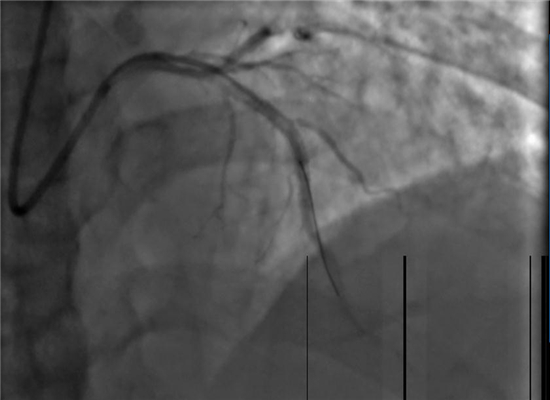

手术之后